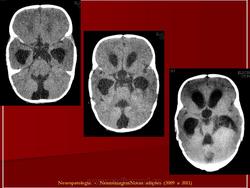

Папилломы сосудистых сплетений.

1.pap_.slayd308.jpg2.pap_.slayd309.jpg3.pap_.slayd310.jpg